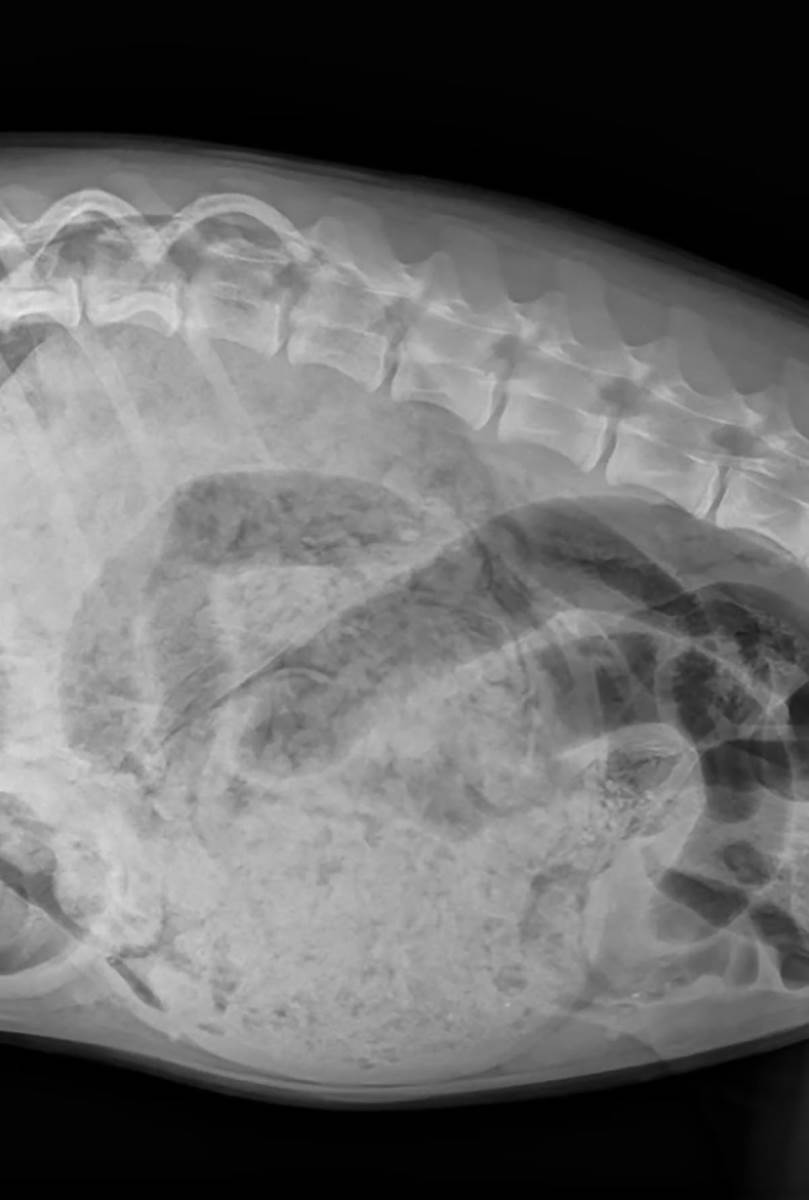

Pas pojeo 24 čarape, kombinezon i gumice za kosu: Veterinari se krstili kad su pogledali rendgen snimak